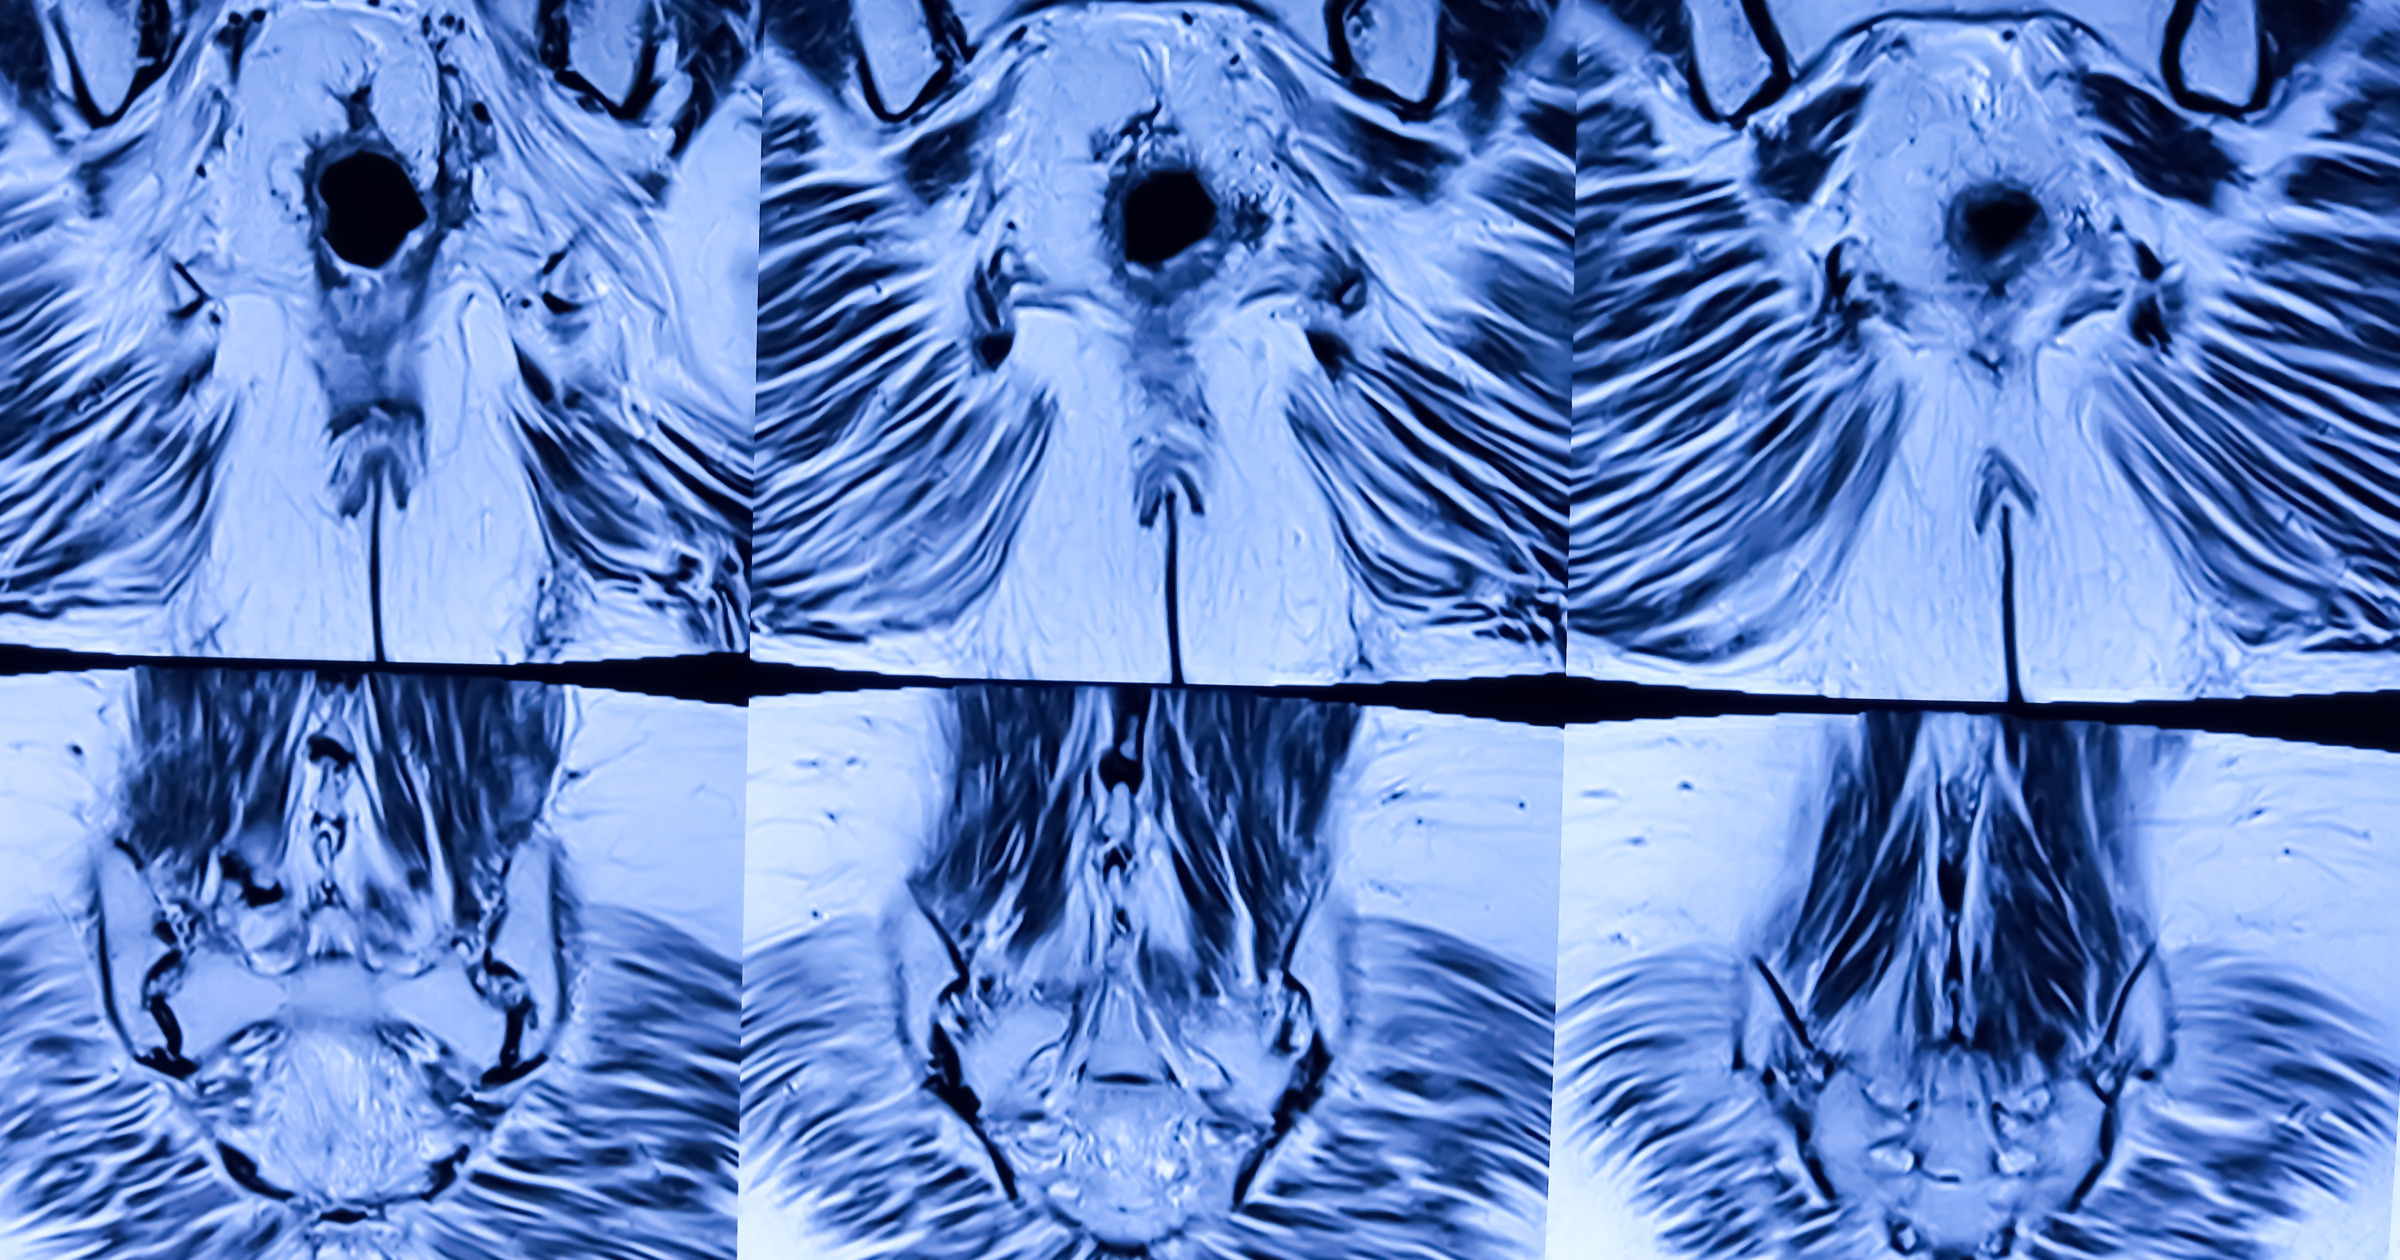

従来の撮像プロトコルでは、T2WIの軸位(Axi)および斜位冠状(obl-Cor)画像を中心に3mm厚で撮影されていました。しかし、2020年以降、多くの施設で共同研究用の新プロトコルが採用され、撮像技術は大きく進化しています。近年では**高分解能撮像(High Resolution: 0.6mm×0.6mm)**が可能となり、微細な構造の識別がより明確になっています。また、撮像時間の短縮と高画質化を両立させるため、SSFSE(Single Shot Fast Spin Echo)にDLR(Deep Learning Reconstruction)を組み合わせた撮像が導入され、骨盤全体像をわずか30秒以内で取得できるようになっています。さらに3D-T2WでもDLRを併用することで、三次元的な再構成による腫瘍の立体的把握が容易となりました。

※当院のMRI画像

こうした技術的進歩により、MRIによる直腸がんの評価は単なる「腫瘍の存在診断」から、「手術戦略立案のための機能的画像診断」へと進化してます。特に、**腫瘍の短軸像(short-axis view)**は臨床的に最も重要であり、CRM(circumferential resection margin:環周切除断端)やEMVI(extramural vascular invasion:血管外浸潤)といった予後因子の評価において必須の情報を提供できます。